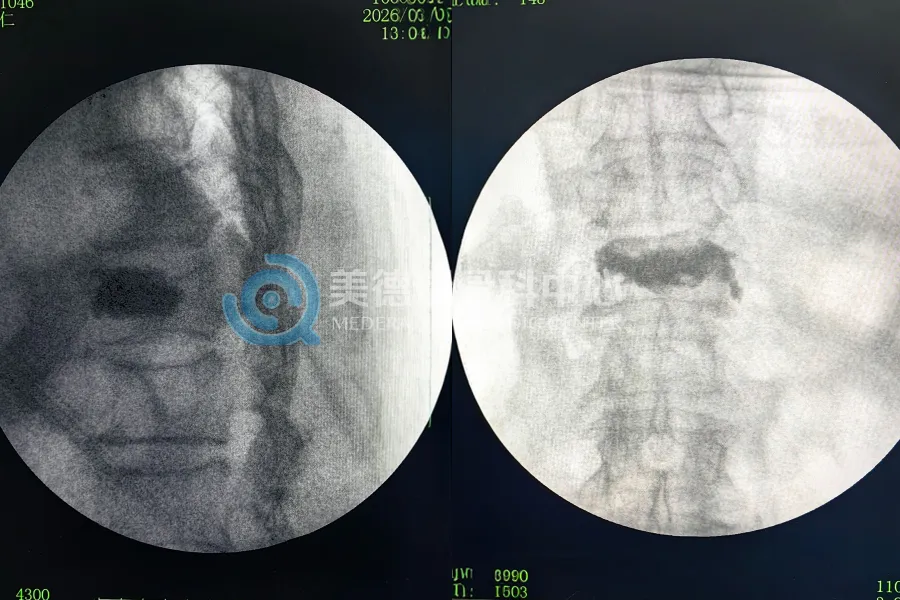

节后一周的手术中,针对多位80岁以上高龄患者普遍存在的骨质疏松性椎体压缩性骨折,翁牛特旗与焦作美德瑞骨科中心分别实施了多例经皮骨水泥成形术(PVP),在缓解疼痛的同时,更重要的是让老人家能尽早下床,避免了长期卧床可能引发的各种并发症。

对于此类高风险病例,美德瑞的价值不仅体现在手术台上的精准操作,更在于系统性的术前评估与麻醉和围手术期监护。在集团统一的临床路径指导下,即使是基层合作医院,也能通过标准化的MDT(多学科协作)运作机制,为高龄、多基础疾病的患者提供具备确定性的医疗安全保障。